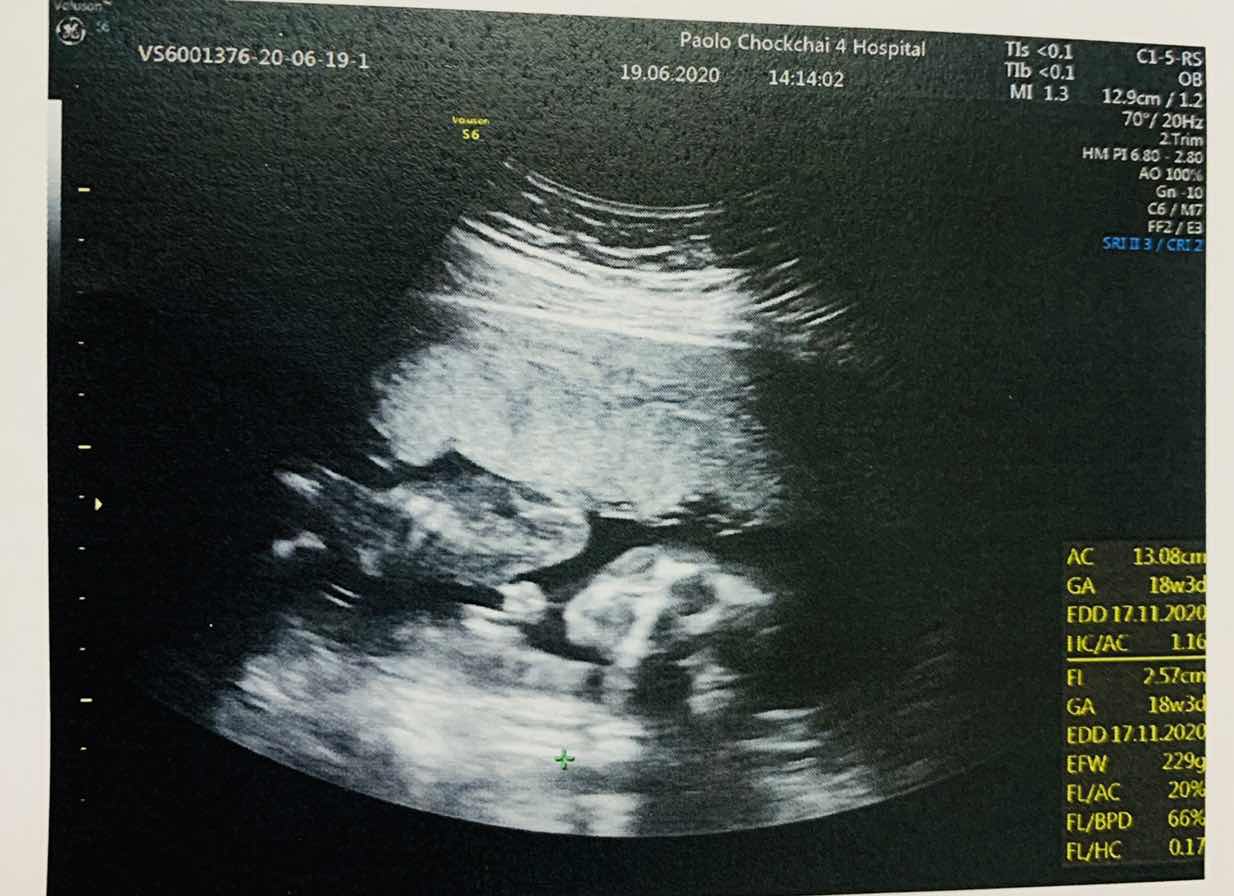

อยากเห็นใบซาวด์ทีมพฤศจิ😍

มาอวดกันเร็ววว🥰🥰 บ้านนี้13 พฤศจิ